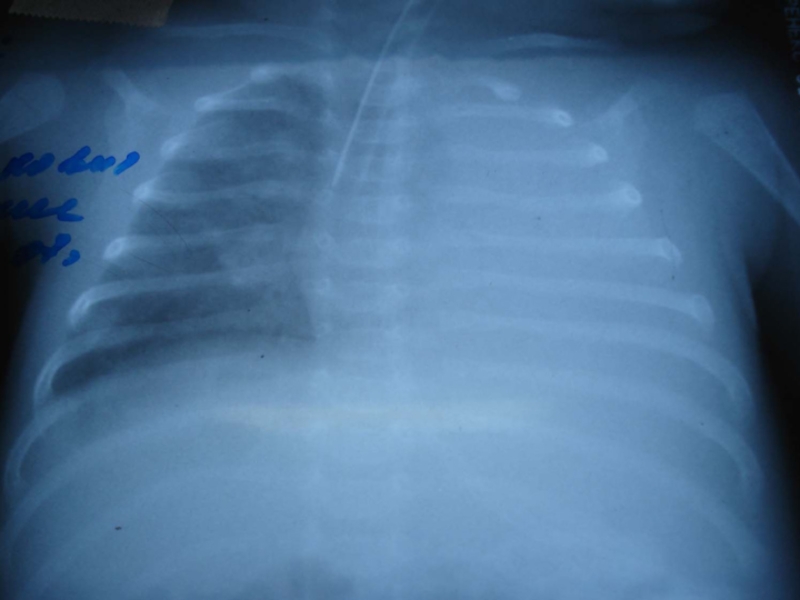

Глубина стояния ЭТТ должна уточняться Rö-графически

ВСЕГДА

Размер ЭТТ у новорожденныхГлубина стояния ЭТТ должна уточняться Rö-графическиВСЕГДА

Слайд 22Осложнения, возникающие после интубации в процессе ИВЛ

С наружи трубки:

перегиб , примыкание скоса к стенке трахеи, грыжевое

выпячивание манжеты

Внутри трубки:

закупорка просвета слизью, кровью

разрыв трахеи или бронхов

смещение трубки, ателекта, экстубация

Осложнения, возникающие после интубации в процессе ИВЛ   С наружи трубки:   перегиб , примыкание